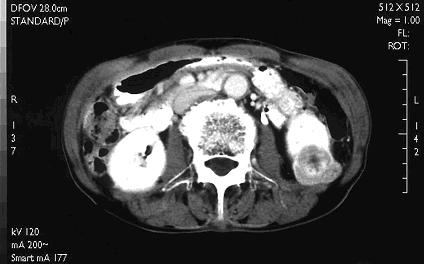

② CT検査

腎細胞がんに診断でもっとも大事な検査です。造影剤を使用して撮影する事により腫瘍の性状の判定に役立ちます。同時に転移や静脈内に伸びた腫瘍塞栓の有無を診断できます。